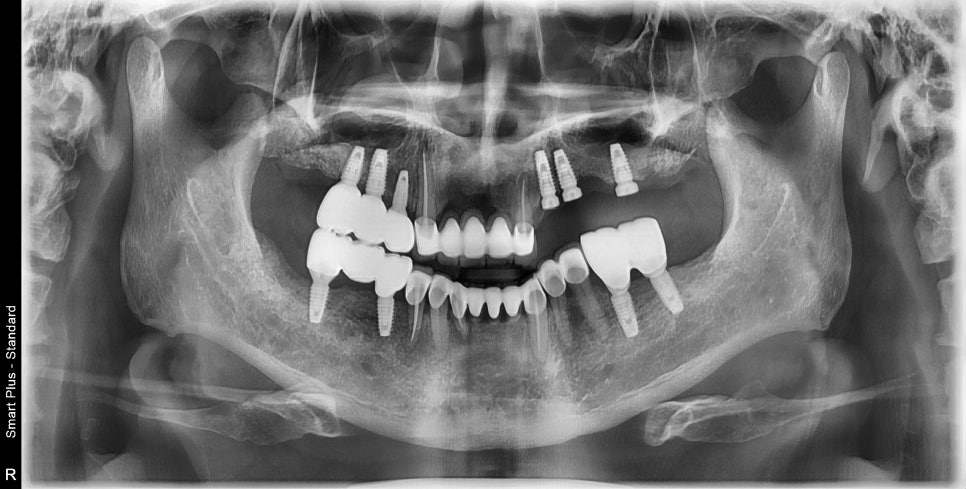

임플란트의 머리가 올라간뒤 모습입니다.

치아가 빠지고 너무 오랜기간 방치하게 되면 임플란트를 심어야 하는 부분의 공간이 옆 치아가 쓰러져 들어와서 사라지기도 하고

뼈가 줄어들어서 임플란트 식립시 많은 뼈이식을 하거나 임플란트가 불가능해지기도 합니다.

많은 일들이 미루면 큰일이 되는데

특히 치과쪽은 미리하지 않으면 더 큰 공사가 되는 것 같습니다.